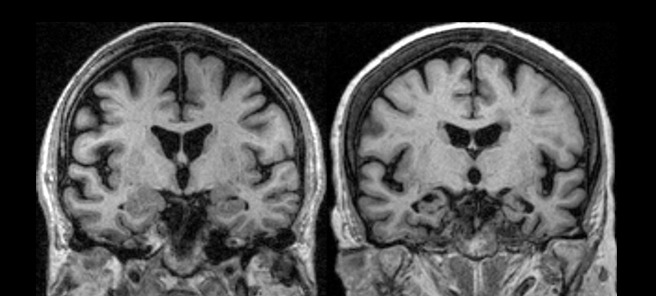

https://adsense.google.com/adsense/u/1/pub-9161951367286286/myads/sites/preview?url=notion6988.tistory.com 🧠 “나이 탓 아니다”… ‘이런 어려움’ 있다면 치매 신호일 수 있습니다